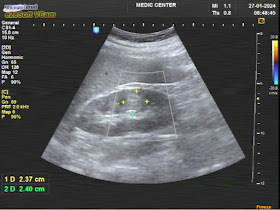

Ultrasound detected a # 86x106 mm right pelvic cystic tumor which was in front of the sacrum-coccyx and elevated the rectum from behind. It may a GIST but could not ruled out of an ovarian tumor.

Both two kidneys were in hydronephrosis without stone, may due to be pressed in pelvic region.